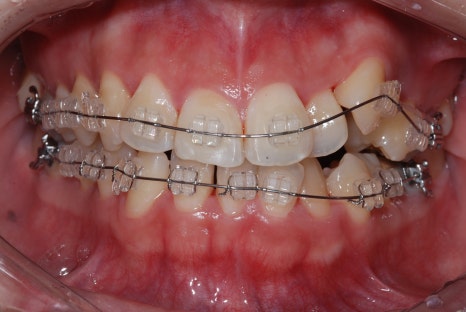

덧니 교정은 치아 자체를 움직여서 배열을 바르게 만드는 치료인데요.

시간이 걸린다는 점에서 단기간 결과를 원하는 분들에게는 망설여지는 선택일 수 있지만,

장기적으로는 가장 근본적인 해결책이라고 말씀드릴 수 있습니다.

교정 치료를 통해 덧니를 가지런히 배열하면

심미적인 개선뿐 아니라 구강 건강까지 동시에 잡을 수 있는 건데요.

덧니 비발치 교정

물론 모든 환자분들이 교정을 해야 하는 건 아닙니다.